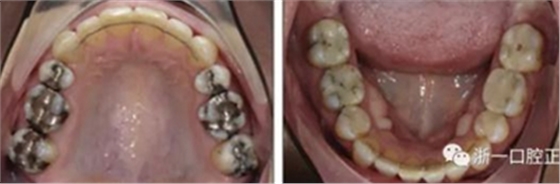

患者曾行正畸治療,現(xiàn)覺笑容不美觀前來就診。患者正面觀及側(cè)貌示下頜發(fā)育不足,偏高角,唇閉合不全。上下頜中線齊。覆合、覆蓋4毫米。磨牙關(guān)系及尖牙關(guān)系II類。上頜擁擠度4mm,下頜擁擠度6mm。4顆第一前磨牙在第一次正畸治療時已拔除。上下牙弓呈尖圓型,牙弓狹窄。

因此最終,我們決定采用手術(shù)輔助快速擴弓進行上下頜擴弓,上頜行腭中縫切開術(shù)、下頜行正中劈開后使用hyrax擴弓器進行擴弓。擴弓完成后再使用固定矯治器進行矯正。

擴弓保持8周后,除擴弓器影響牙外粘接托槽,使用0.014鎳鈦絲進行排齊、整平。旋轉(zhuǎn)停止后3個月拆除擴弓器,全口粘接托槽,使用0.016niti繼續(xù)排齊整平。佩戴可摘保持器,保持上頜寬度。在使用至0.018x0.018niti7周,徹底排齊整平后,使用大弓型的0.016x0.022不銹鋼絲,繼續(xù)維持原有寬度,同時停止使用可摘保持器。掛II類牽,糾正磨牙關(guān)系,使用鏈圈關(guān)閉散在間隙,少量使用IPR去除局部前牙的黑三角。術(shù)后9個月拍全景示,牙根平行度可,再無其他牙根出現(xiàn)問題。1年7個月后治療結(jié)束。上下頜3-3舌側(cè)保持器+哈雷氏保持器進行保持。

患者側(cè)貌改善,下唇唇肌緊張消失,上下唇可自然閉合。磨牙及尖牙關(guān)系糾正至I類,覆合覆蓋正常。上下頜弓型糾正至卵圓形,牙弓寬度增加。頭影測量分析示SNA角81.8°,ANB角3°。頭影測量重疊圖示下頜骨向后旋轉(zhuǎn),垂直面高度略有增加。